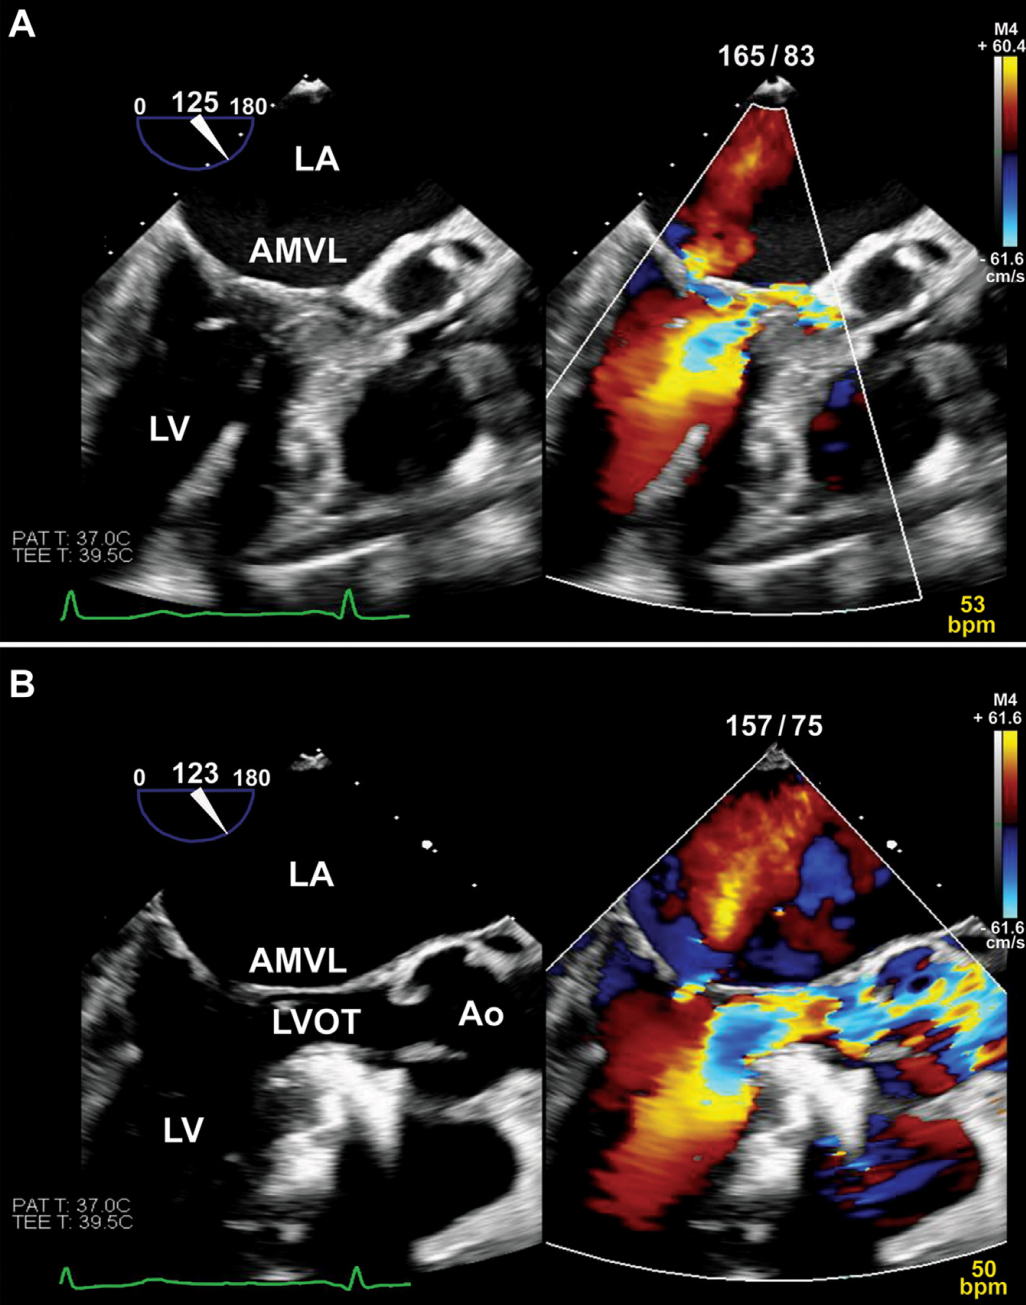

消融后即刻经食道超声示LVOTO峰值压差由94mmHg降至19mmHg,二尖瓣前叶SAM消失,二尖瓣反流减轻(图5)。最显著的是收缩压升高,患者在离开导管室前已完全停用所有升压药(图3B)。术后第1日经胸超声示静息LVOTO 20mmHg,Valsalva动作时为24mmHg。

图5 术中超声

(A)消融前:经食管超声心动图显示SAM及中度二尖瓣反流;(B)消融后:经食管超声心动图显示SAM消失,二尖瓣反流减至轻度。